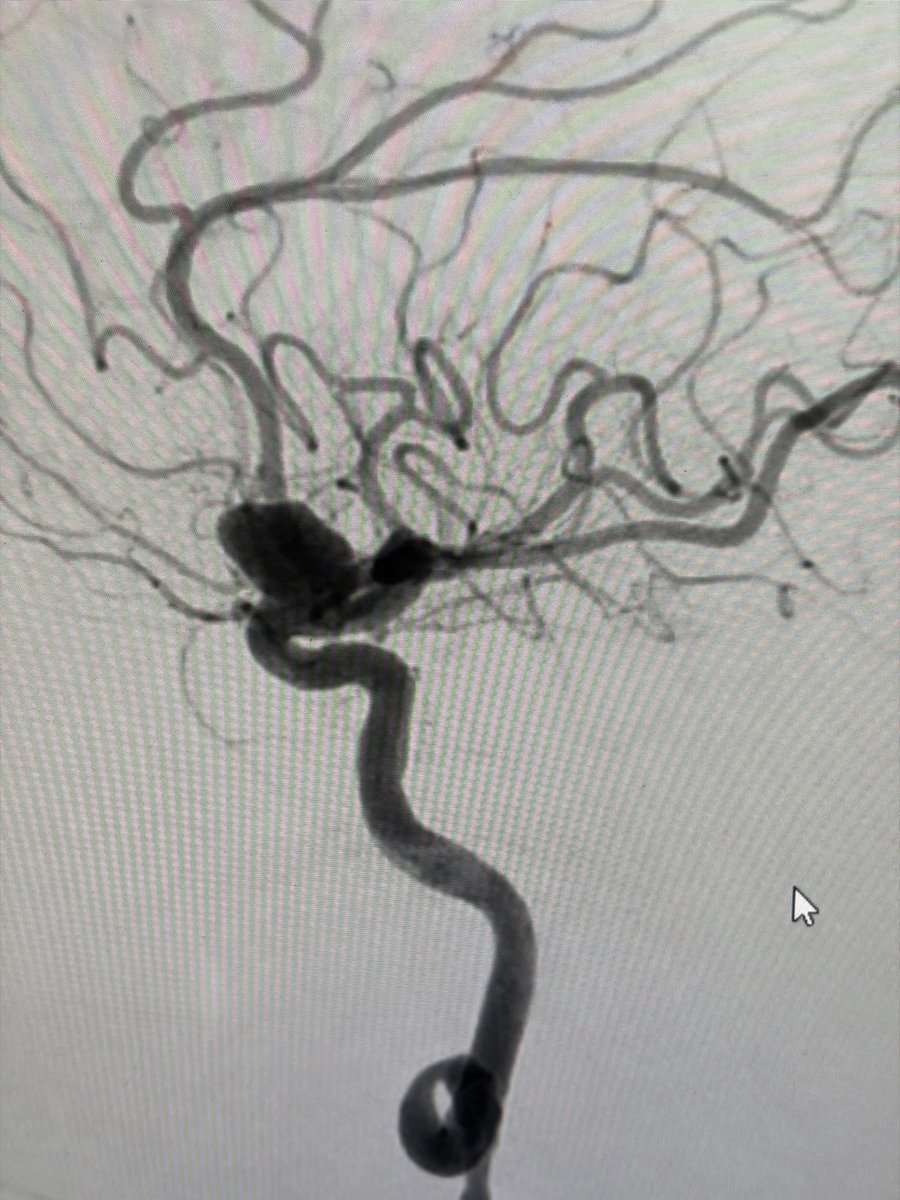

Two weeks ago, a 54-year-old patient recovering from open-heart surgery (CABG) suffered a major stroke. • Symptoms: Sudden inability to speak + right-side paralysis. • Action: Immediate Mechanical Thrombectomy to remove the brain clot.

Manish Kumar Yadav tweet mediaManish Kumar Yadav tweet mediaManish Kumar Yadav tweet mediaManish Kumar Yadav tweet media